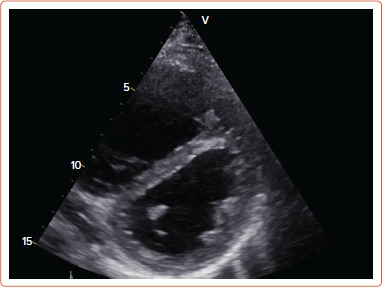

Abstract Image